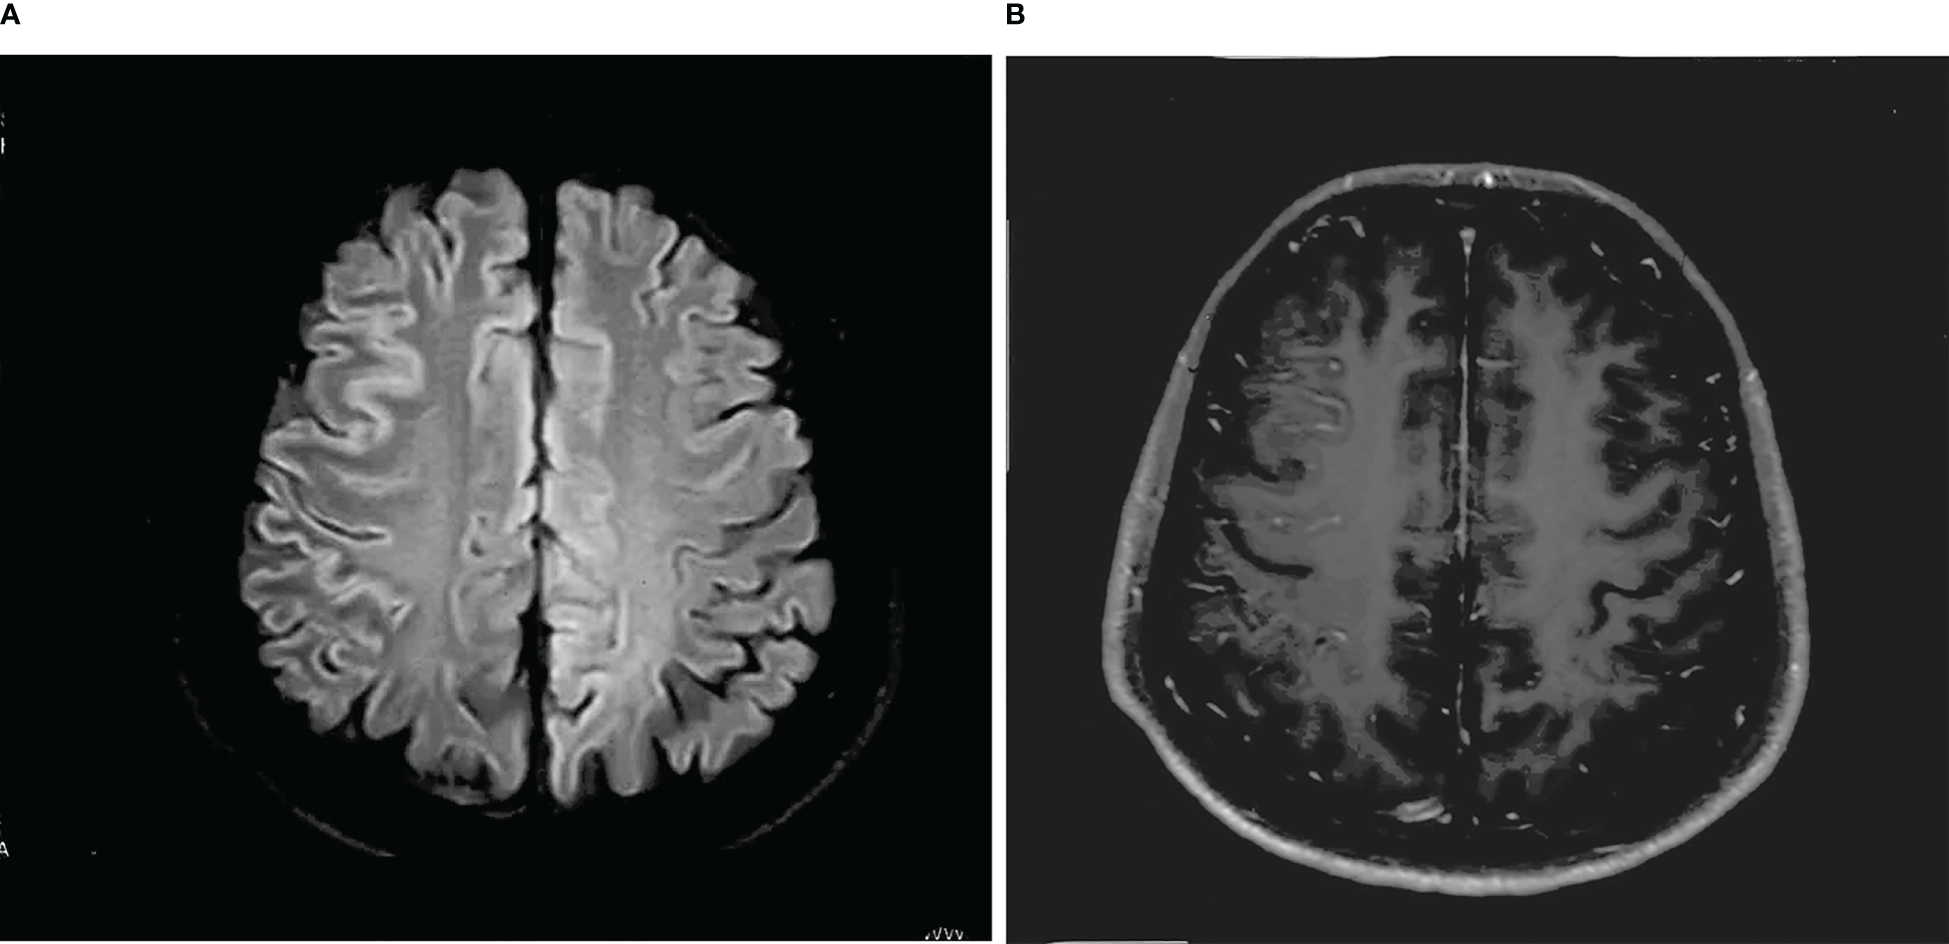

Figure 2

(A) T-2 FLAIR hyperintensity in the right frontal cortex, swelling of brain tissue, and shallowing of the cerebral sulcus. (B) Abnormal enhancement of the pia mater in the right frontal lobe.